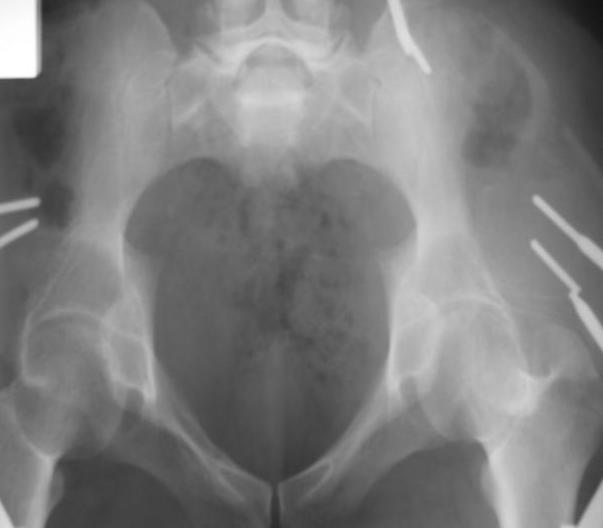

Поступил пациент после кататравмы (упал с высоты 4м). После обследования установлен Ds: Сочетанная травма. ЗТГК перелом 5-6 ребер справа. Ушиб левого леогкого. Оскольчатый перелом крыла подвздошной кости слева, со смещением. в экстренном порядке выполнена операция о/синтез таза стержневым аппаратом. Снимки прилагаются. Пациент со 2-го дня стал ходить без костылей. Из анамнеза жизни у пациента имеется гепатит В и С, с 1998г. употребляет наркотики (героин 1г в день нормальная доза). На контрольных снимках таза в аппарате смещение отломков сохраняется, да еще и стержни сломались. Подскажите ув.коллеги, как поступить в данной ситуации: оставить все как есть или добиваться репозиции в аппарате, или планировать на открытую репозицию. На сегодняшний день пациент стабилен, по анализам компенсирован. Принимает героин по другому справиться не может. С ув. Андрей

Уважаемый Андрей, у пациента имеется перелом передней колонны,и после наложения аппарата положение отломков ухудшилось. возможно не из-за ваших действий а за счет тяги четырехглавой мышцы. Обе ости настойчиво будут тянуть крыло вниз.